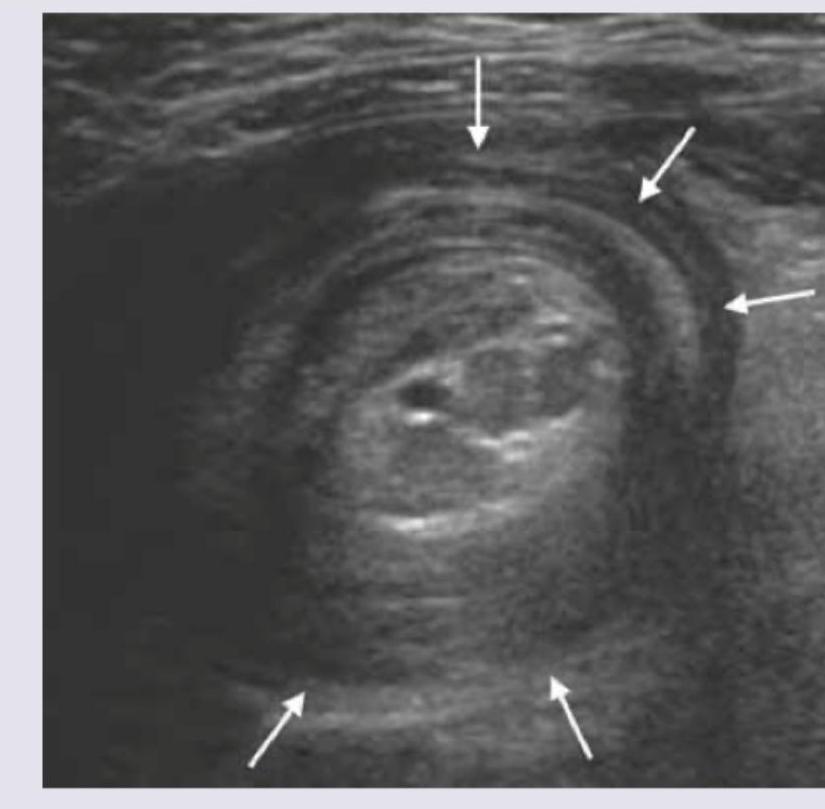

The ultrasound finding of a 7 -month-old child with abdominal pain and mass in the upper abdomen is shown below. What is the diagnosis? (NEET Pattern 2018)

Explanation: ***Intussusception*** - The ultrasound image clearly shows a "target sign" or "doughnut sign," which is pathognomonic for **intussusception**, where one segment of the intestine telescopes into another. - This condition commonly presents in infants (around 6-36 months) with **abdominal pain**, an abdominal mass, and sometimes **currant jelly stools**. *Intestinal volvulus* - **Intestinal volvulus** involves the twisting of the intestine around its mesentery, which would typically show a "whirlpool sign" on ultrasound due to twisted mesenteric vessels, not the "target sign." - It usually presents with sudden onset of severe abdominal pain, bilious vomiting, and signs of intestinal obstruction and ischemia. *Pyloric stenosis* - **Pyloric stenosis** is characterized by hypertrophy of the pyloric muscle, which would appear as an elongated, thickened pyloric canal on ultrasound with increased pyloric muscle thickness (>3mm) and length (>15mm). - Clinical presentation involves non-bilious projectile vomiting in infants, typically between 2 and 8 weeks of age, not at 7 months with an abdominal mass and the bowel-within-bowel appearance shown. *None of above* - The classic ultrasound findings and clinical presentation strongly point to intussusception, making this option incorrect.